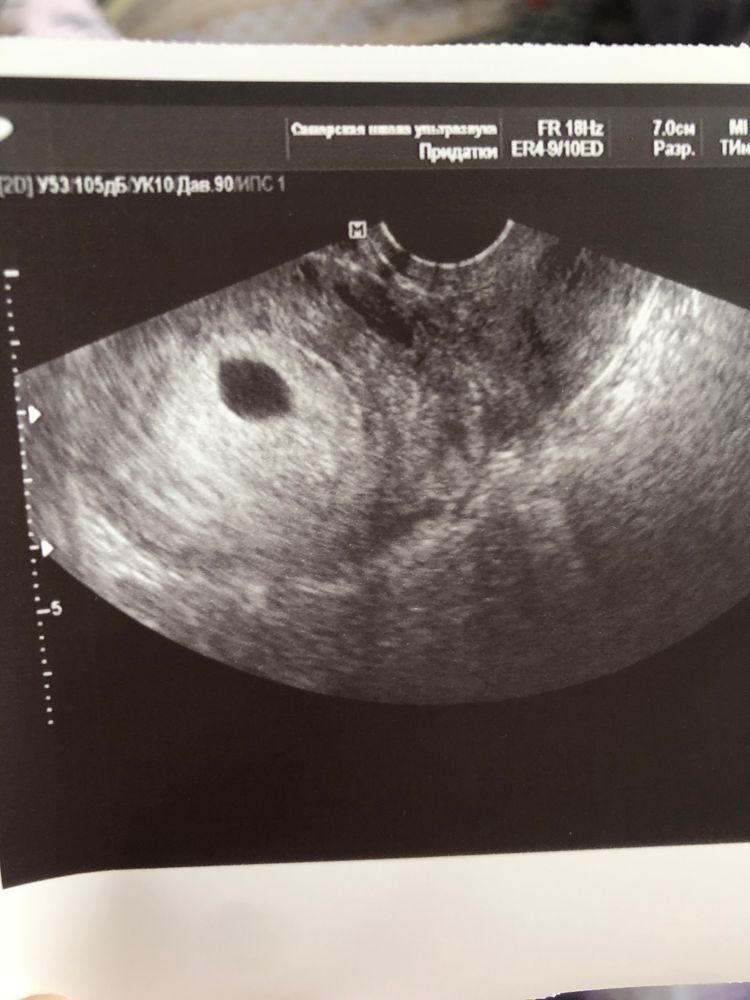

Помогите ждать или нет эмбриона? 8я неделя

Месячные были 15 октября, срок 8 недель.

3 декабря сдавала хгч 16519 через 4 дня 19862

3 декабря свд пя 11,5мм нет жм и эмбриона. Поставили неразвивающую б. Сегодня 9 декабря опять сходила на узи. Свд пя 12,5 мм стал. Так ничего и не обнаружили больше. сказали делать мед аборт.